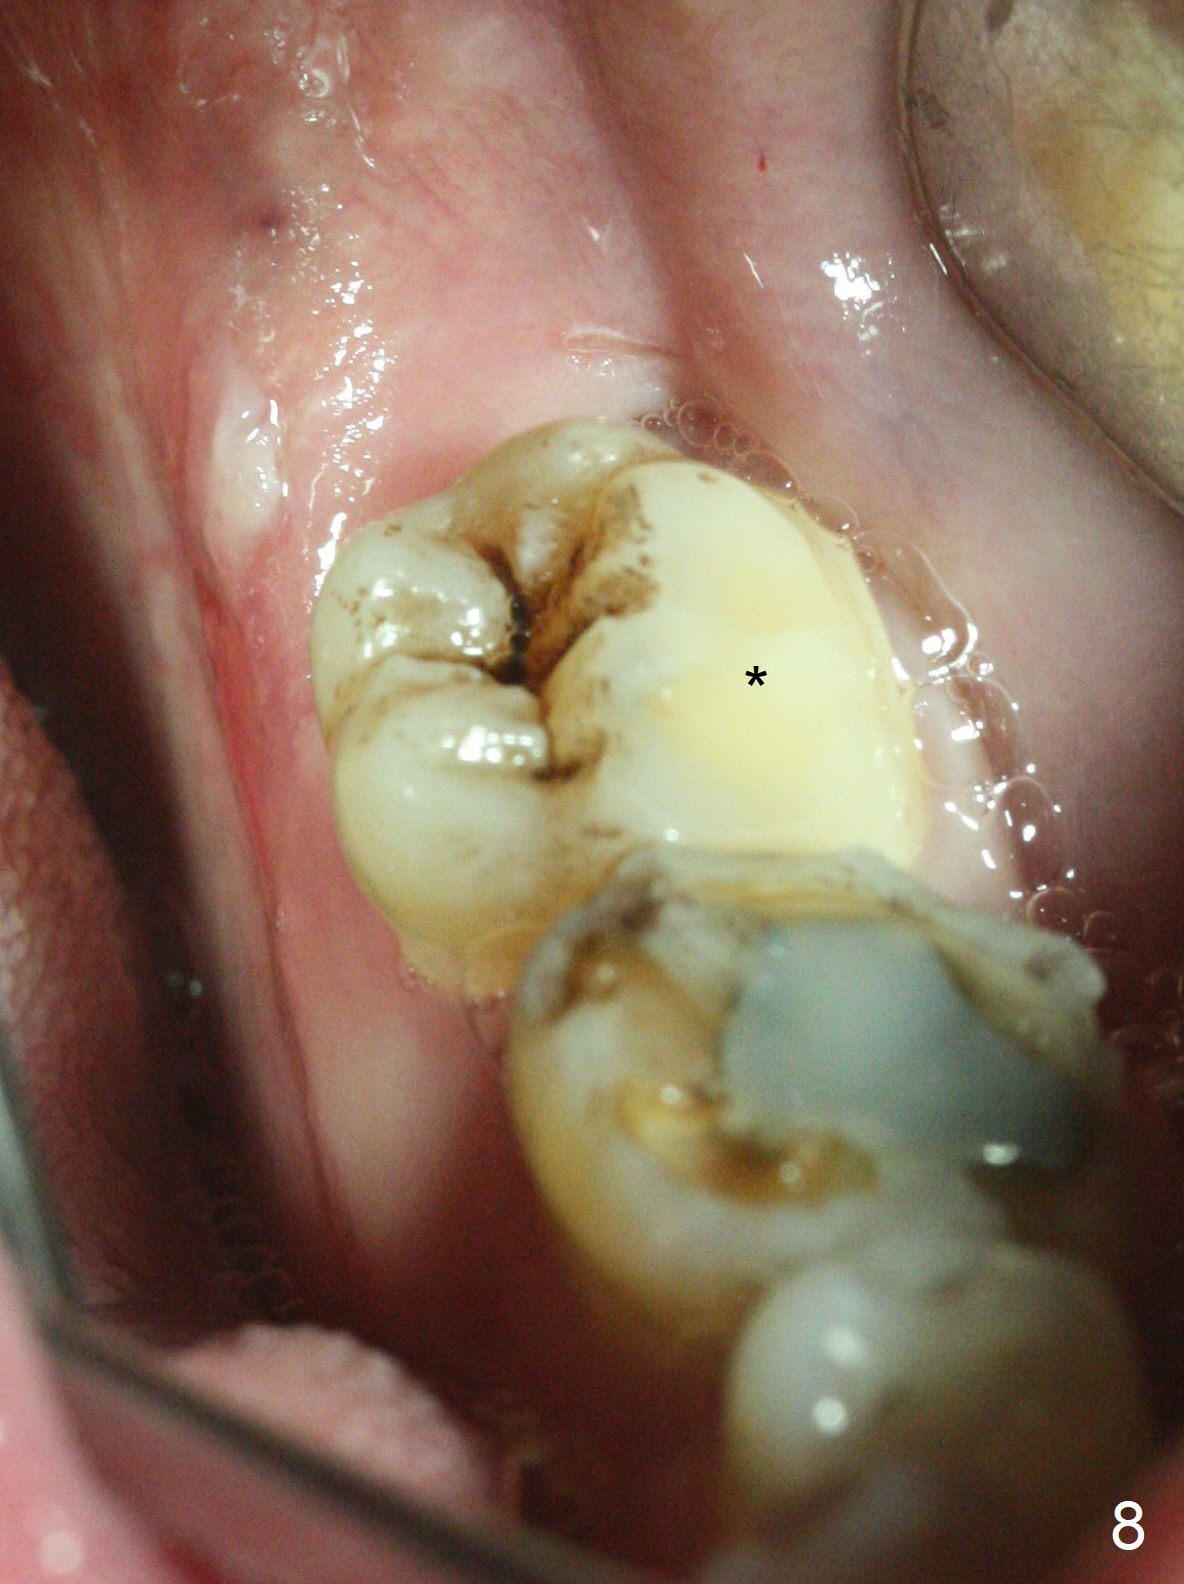

Photos are taken to show occlusal wear (bruxism) of the teeth #31 and 17 (Fig.7,8) prior to #17 extraction. Osteogen plug is placed in #17 socket after extraction and SRP at #18. The bone height at #18 distal seems to increase 2 years 4 months post extraction (Fig.9-12). The 1st molars have enamel hypoplasia with occlusal wear. In addition, occlusion is abnormal. There is no centric occlusion, partially contributing to periodontitis at #15 and 18. Crown is planned at #19 because of loss of occlusal amalgam (Fig.11 A, 12). Orthodontics may be required, although 2 insurances do not have orthodontic coverage for adults.